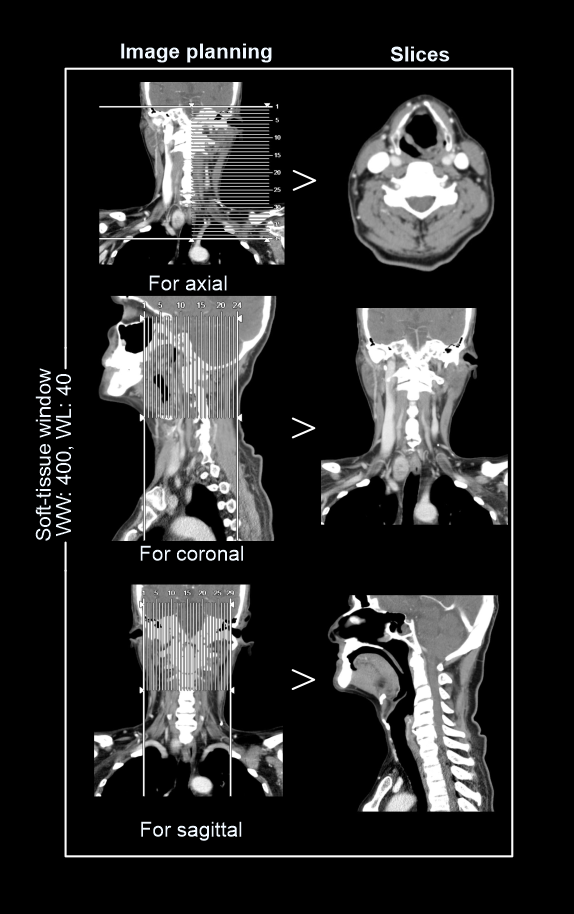

- Axial, coronal and sagittal images in soft-tissue window (WW: 400, WL:40), without exceeding 3mm slice thickness.

- Additionally, a suitable image in bone (WW: 3500, WL:350) window, displayed in any plane, without exceeding 3mm slice thickness.

- For vocal cord neoplasms, 1mm thin sections of multi planer reformats (MPR) are helpful insoft-tissue window limited to the larynx, and axial slices are reformatted parrel to the vocal cords or hyoid bone – refer Neck non-contrast article for images.